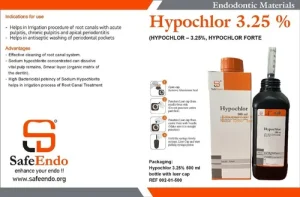

₹450 Original price was: ₹450.₹285Current price is: ₹285.

Features- Antimicrobial Action: Effective against a broad spectrum of bacteria, fungi, and viruses, making it ideal for endodontic treatments. Biofilm Disruption: Aids in breaking down biofilms within root canals, enhancing disinfection. Compatibility: Can be used with various irrigation systems and is compatible with common endodontic materials. Ease of Use: Designed for easy application through…